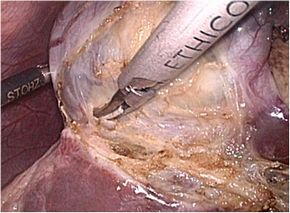

手術が適応になった場合は原則、腹腔鏡下胆嚢摘出術を施行します。

腹腔鏡下胆嚢摘出術とは、腹部に4カ所の穴(今後10mm→5mmの可能性)を開け、その穴から内視鏡や手術鉗子を挿入し、胆嚢を摘出する方法です。この術式の利点は傷が小さく、術後の痛みが少なく回復が早いことです(身体にやさしい胆石手術)。ただし癒着が高度な場合や、胆嚢の炎症、萎縮や肥厚などが強い場合には開腹手術に移行する可能性もあります。

手術画像